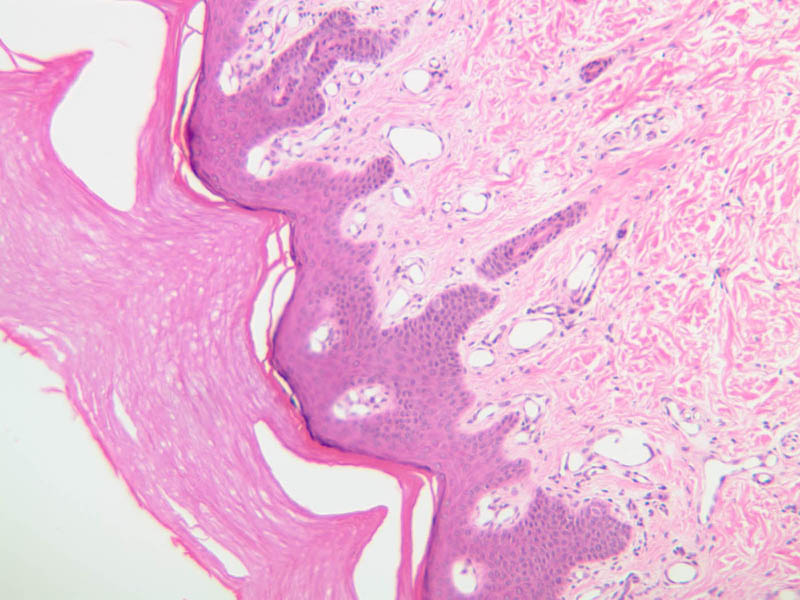

For general orientation, note that skin has two components, epidermis (a stratified squamous epithelium) and dermis (a connective tissue layer beneath the epidermis). Epidermal ridges project into the dermis, enclosing between them the highly vascular dermal papillae. Beneath the dermis lies the subcutaneous tissue, a loose layer of connective tissue, fat, blood vessels, and nerves. The skin appendages are situated partially in the dermis and partially in the subcutaneous layer. The skin consists primarily of two cell types; a keratin-producing epithelial cell (keratinocytes) and a pigment cell of neural crest origin (melanocyte). Langerhans cells are also present. These are believed to be antigen presenting cells of the epidermis. The keratinocytes exhibit morphological and functional stratification from base to surface of the epithelium and thus provide a basis for distinguishing several layers of the epidermis.

Examine slide A-50 (fingertip, H&E [2.5x, 10x-labeled, 20x, 40x-labeled] [20x, 40x] [10x, 20x, 40x] [20x, 20x, 40x]), and study the morphology of five layers of thick skin. The deepest part of the epidermis comprises the stratum basale which provides the cells required for continual renewal of the epidermis. This stratum is composed of a single layer of columnar or cuboidal epithelial cells attached to the basement membrane.

Superficial to the stratum basale is a multi-cellular layer known as the stratum spinosum, consisting of polyhedral cells that have a "prickly" or spiny appearance (A-50, langerhans cells [10x, 20x-labeled, 40x-labeled] [40x, 40x-labeled, 40x, 40x-labeled]; A- 48, abdominal skin, H&E [10x, 20x, 40x] [40x, 40x, 40x, 40x]). The spiny cells are separated by intercellular spaces that are bridged at numerous points by cytoplasmic processes, which in turn are bound together by desmosomes. The cytoplasmic processes projecting on all sides from the cells give them the spiny appearance to which the name refers. These are best seen under high power. Langerhans cells can also be found in this layer.

The stratum lucidum is often considered to be a subdivision of the stratum corneum. This layer is evident only in thick (glaborous) skin. It appears as a clear band beneath the stratum corneum. Cells of the stratum lucidum are well advanced in the process of keratinization. Consequently, the nucleus and many of the cytoplasmic organelles become disrupted and disappear as the cells become filled with the intracellular protein keratin. In many specimens, there is a separation artifact at this point. The outermost layer of the epidermis is called the stratum corneum and is composed of fully cornified (keratinized) remnants of epithelial cells ([40x]). It has a basketweave appearance. The close union of the resulting scales with each other, and their content of insoluble protein and extracellular lipids, provides a barrier to diffusion between the body and its external environment.

Locate a hair follicle cut in cross section (slide A-49, embryo scalp [2.5x, 10x, 20x, 40x] [2.5x, 10x, 20x-labeled, 40x]; A-59, scalp [2.5x, 10x, 20x, 40x]; A-58, axilla [10x, 20x, 40x-labeled]). It will have the appearance of a series of concentric rings. The outermost ring is a layer of condensed connective tissue. Interior to the connective tissue can be seen the thickened basement membrane of the hair follicle. Inside the basement membrane is the epithelial root sheath. Cells in the outer part of the root sheath are non-keratinized and appear clear; cells of the inner root sheath are keratinized and form a cuticle with cells overlapped downwards. The hair shaft lies inside the epithelial root sheath. The shaft cuticle consists of keratinized cells which overlap upwards and interdigitate with the follicle cells. Inside the hair cuticle, the cortex of the hair represents the innermost circle. It consists of heavily keratinized, pigmented cells whose individual outlines can no longer be seen. Find a follicle cut longitudinally or obliquely (A-59, scalp [2.5x-labeled, 10x, 20x, 40x, 40x-labeled]). Smooth muscle fibers of the arrector pili muscle are attached to the follicle on the side which forms an obtuse angle with the dermis ([2.5x, 10x-labeled, 20x, 40x] [2.5x, 10x, 20x, 40x]). The arrector pili muscles are small, thin, smooth muscles which are diagonally attached to the hair follicle within the dermis and extend to the epidermis. In the angle formed by the muscle and the hair follicle is located the sebaceous gland. These muscles are under autonomic nervous control (sympathetic).